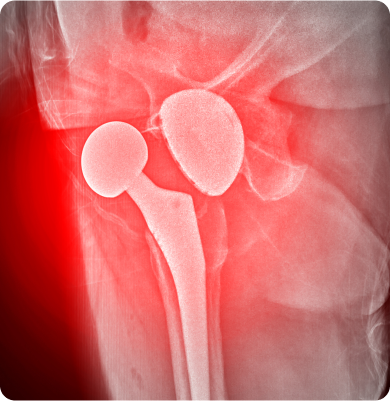

골괴사증(대퇴골두)

뼈에 혈액 공급이 부족해 뼈 조직이 죽고 그로 인해 뼈가 약해지고 변형되는 질환

주요원인

외상, 과도한 알코올 섭취, 스테로이드 약물의 장기 사용, 혈액 순환 장애 등이 주요 원인입니다.

주요증상

• 엉덩이나 고관절에 통증이 발생하며 걷거나 움직일 때 통증이 심해질 수 있습니다.

• 고관절의 움직임이 제한되어 다리의 강직 현상이 나타날 수 있습니다.

• 다리 길이가 비정상적으로 짧아지거나 불균형이 생길 수 있습니다.

고관절 질환 수술적 치료 방법

인공관절 수술(고관절인공관절), 골절 고정술

고관절 질환 비수술적 치료 방법

재활물리치료